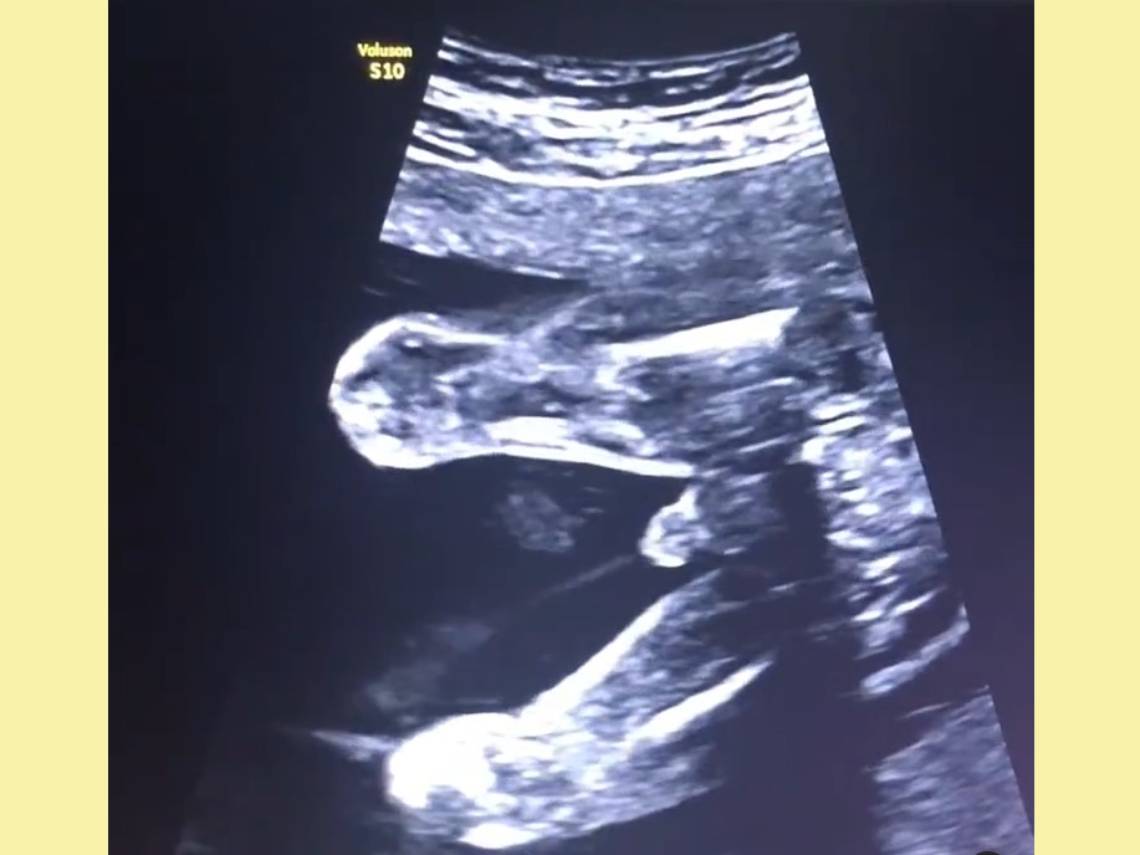

El video del curioso momento

Lo bueno es que gracias a un video podemos observar perfectamente este curioso proceso y ver el momento en el que un peque orina dentro del útero.

Fue publicado por el doctor Ümit Korucuoğlu en su cuenta de Instagram, donde comparte momentos de su vida, pero también de su profesión. No es extraño que en poco tiempo se extendiera por las redes.

Con estas palabras acompañaba la grabación:

“Empezamos el día con la sorpresa que nos ha dado el bebé de mi paciente Begüm en la última revisión 😂 En el video pueden ver la respuesta a la pregunta de si los bebés orinan en el útero 😊 Especialmente después de la semana 20, el componente más importante del líquido amniótico es orina fetal 👍🏻. Que haya las medidas adecuadas de líquido amniótico durante los controles de ultrasonido significa que los riñones están funcionando correctamente y es reconfortante ya que muestra que el bebé está orinando lo suficiente 👏🏻👏🏻”